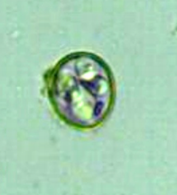

大形馬バベシア(Babesia caballi)、大形のバベシアで、赤血球内虫体は洋なし状(2.15~4.0 x 2.0㎛)と円形、アメーバ状です。